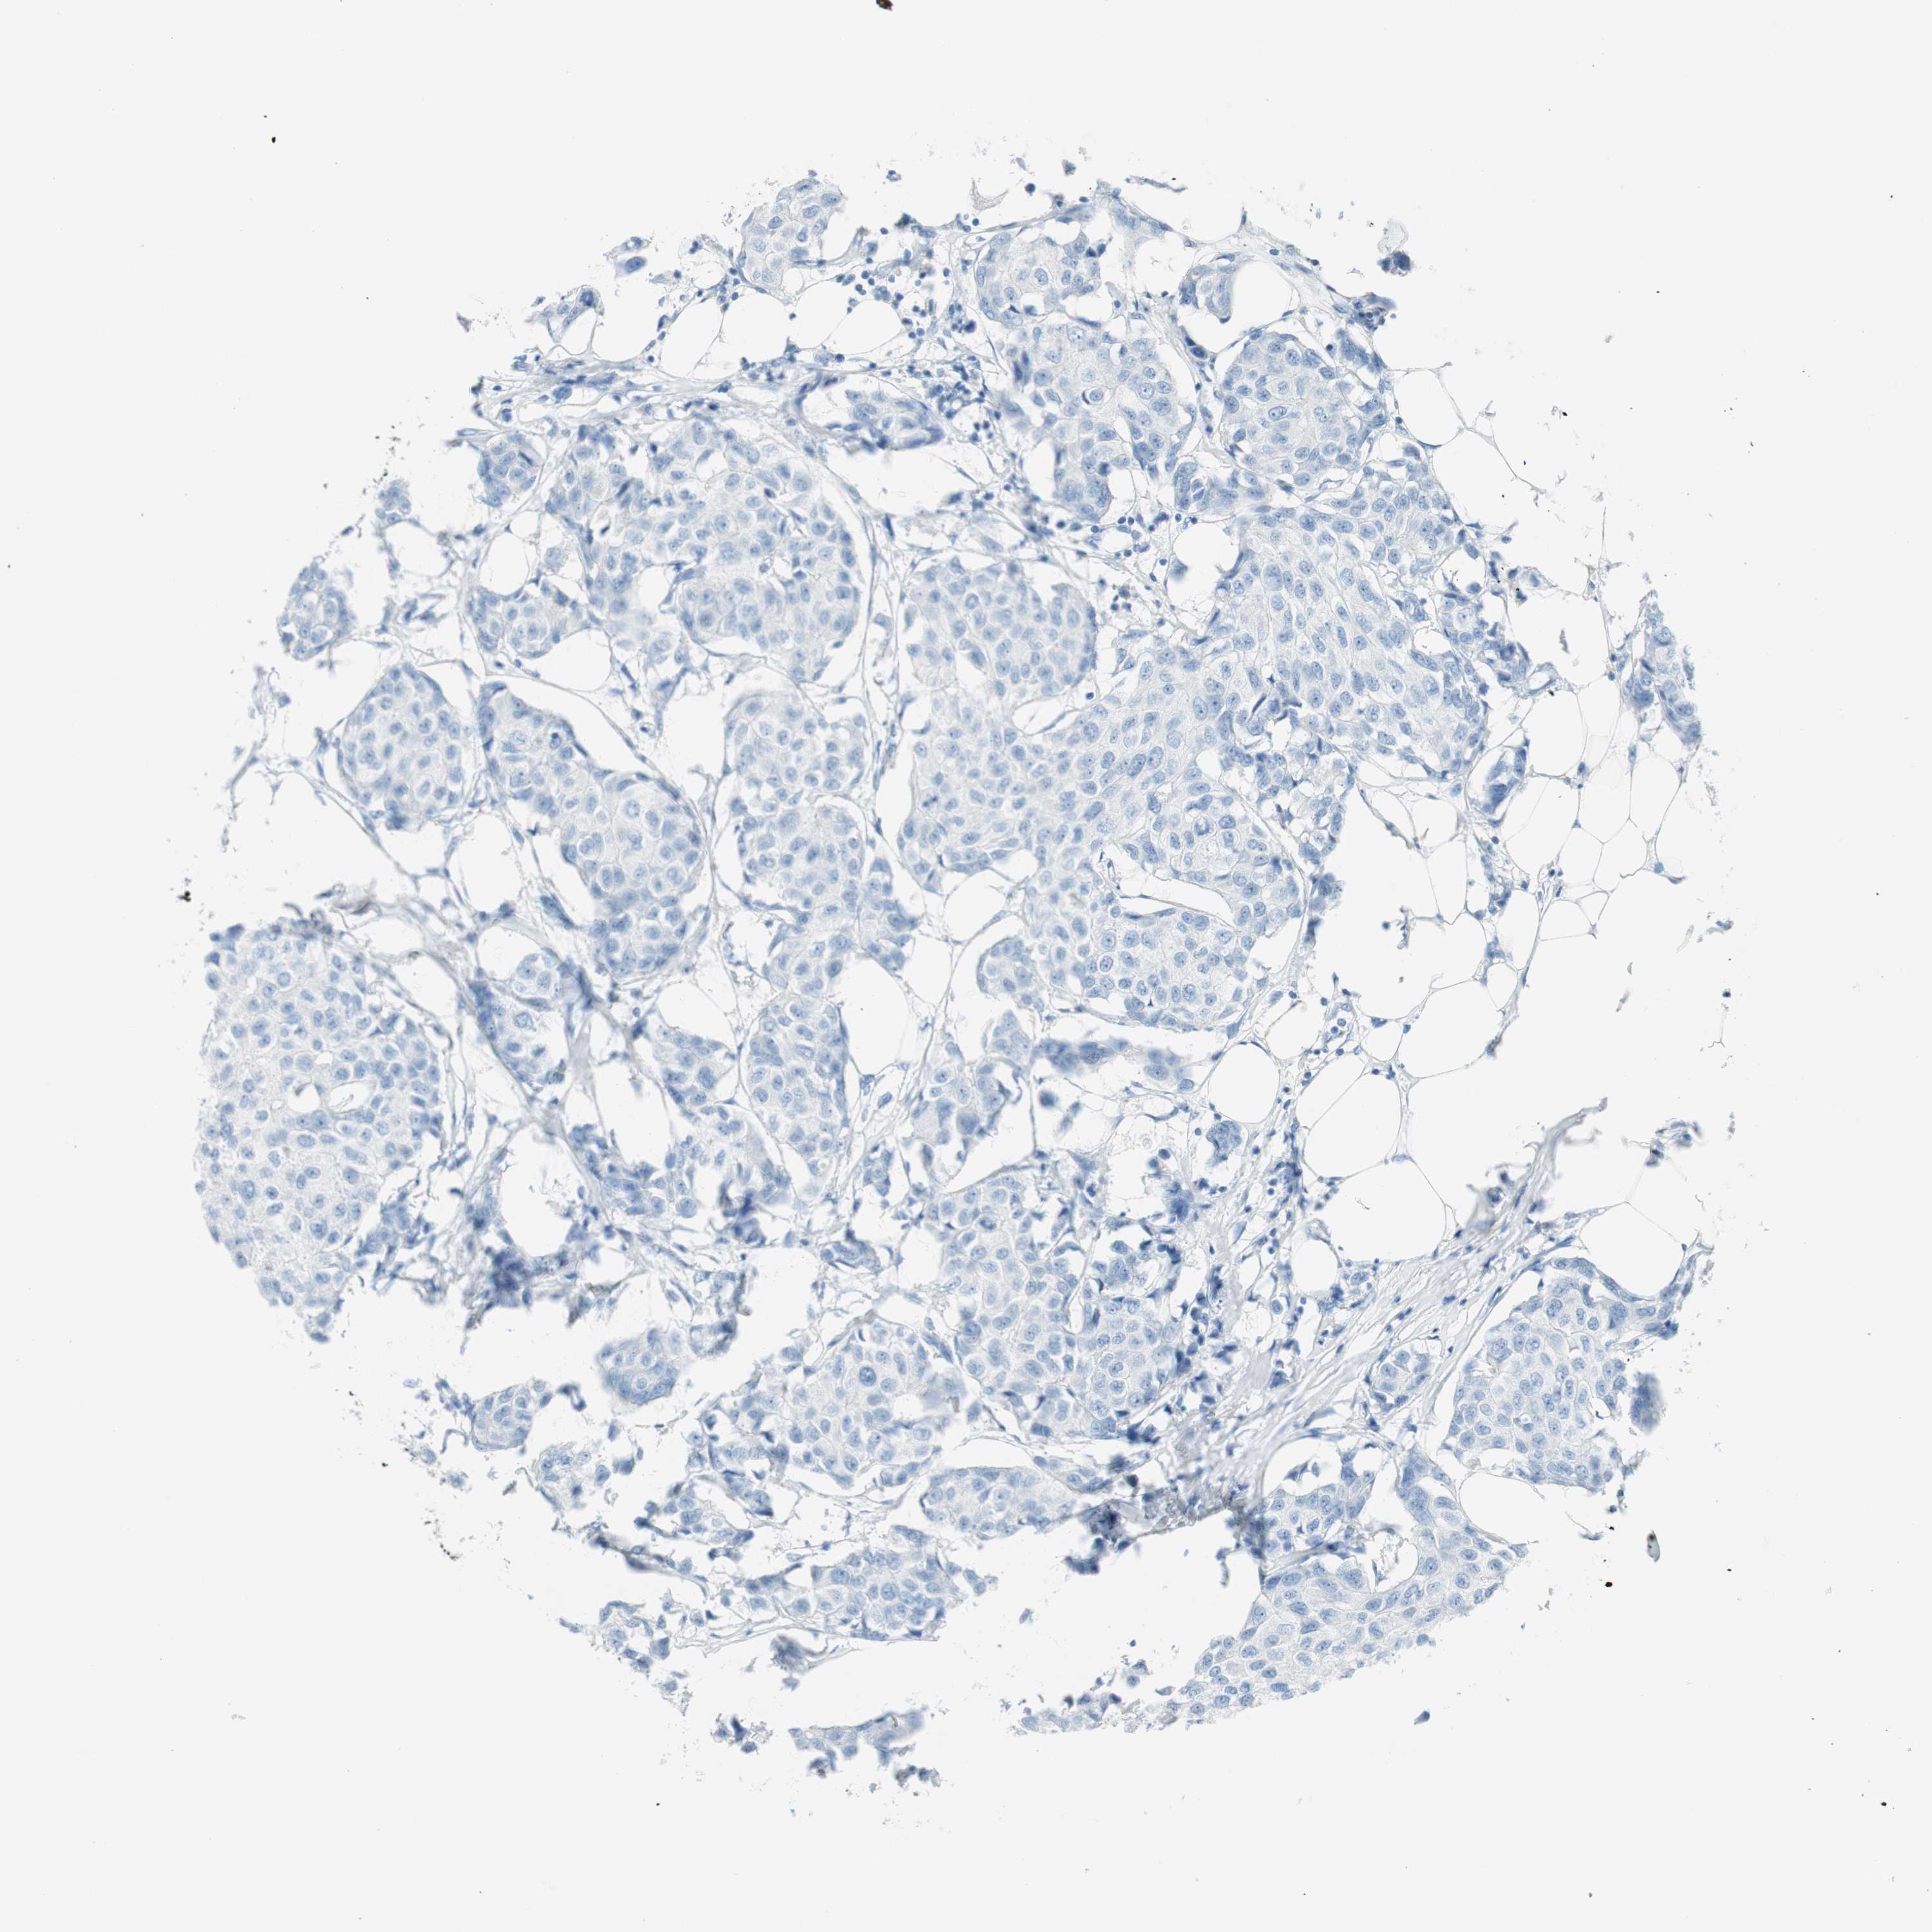

BRCA TCGA BRCA VALIDATION PROTEIN EXPRESSION

ANTIBODIES

AND

VALIDATION